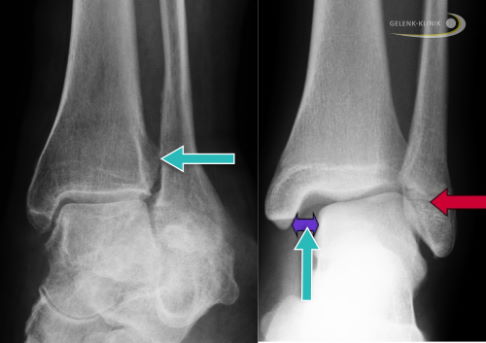

Die Fuß- und Sprunggelenkspezialisten führen bei Verdacht auf Syndesmosebandriss ein röntgenbasiertes Schnittbildverfahren auf beiden Seiten durch, die digitale Volumentomographie (DVT). Die DVT zeigt beim stehenden Patienten , ob die Sprunggelenksgabel unter Belastung aufgeweitet und damit instabil ist. Eine weitere bildgebende Methode zur sicheren Diagnose einer Syndesmosenverletzung ist die noch recht neue und nicht sehr verbreitete Methode der Weight-bearing-Computertomographie (WBCT).

Die Beurteilung der Syndesmosenverletzung ist nach einer DVT-Untersuchung viel genauer möglich als nach Magnetresonanztomographie oder Röntgen. Aktuelle Röntgenaufnahmen ermöglichen dem behandelnden Arzt allerdings, das Ausmaß der gesamten Verletzung einzuschätzen, insbesondere bei begleitenden Sprunggelenkfrakturen. Gerade aufgrund der Häufigkeit eines Syndesmoserisses bei Freizeit- und Leistungssportlern bietet das DVT als bildgebendes Verfahren der Gelenk-Klinik ideale Voraussetzungen für eine exakte Diagnosestellung.

Bei unzureichender Positionierung des Wadenbeins in der Sprunggelenksgabel kann sich im Röntgenbefund unter Belastung und im DVT eine sogenannte Diastase darstellen - ein nach außen hin vergrößerter Abstand der beiden Unterschenkelknochen.

Bei den Kontrollen ermittelt der Orthopäde eventuelle Fehlstellungen sowie den noch bestehende Kontakt der Gelenkpartner im oberen Sprunggelenk. Die hohe Passgenauigkeit (Kongruenz) im Sprunggelenk ist erfahrungsgemäß sehr empfindlich gegenüber Abweichungen: Bereits eine Erweiterung der Sprunggelenksgabel um 1 mm reduziert Studien zufolge die Kontaktfläche um bis zu 40 %. In der Folge werden andere lokale Gelenkabschnitte überlastet und verschleißen.